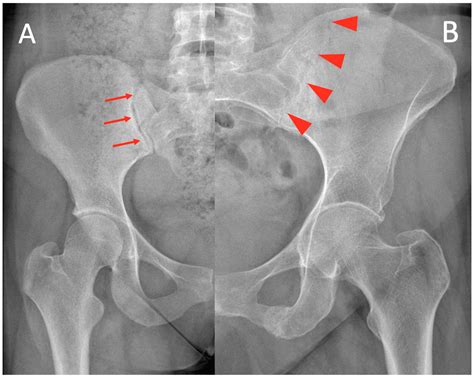

• Identifying Ankylosing Spondylitis: Looking for characteristic signs like erosions or fusion of the joint, which are common indicators of this inflammatory condition.

• Joint Space Width: A narrowing of the joint space often indicates wear and tear or degenerative joint disease.

• Sclerosis: This refers to an increase in bone density around the joint, which is a common response to chronic stress or inflammation.

• Erosions: Small "nibbles" in the bone surface, which are highly suggestive of inflammatory arthritis.

• Ankylosis: The fusion of the joint, where the space between the bones has disappeared entirely.

• sacroiliac joint x ray abnormalities

• sacroiliac joint x ray abnormal